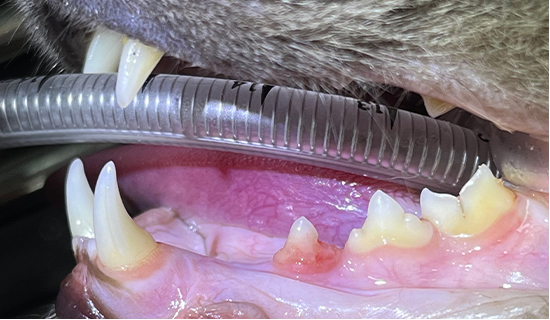

치아흡수병변의 모습과 치아엑스레이 영상(Type2)